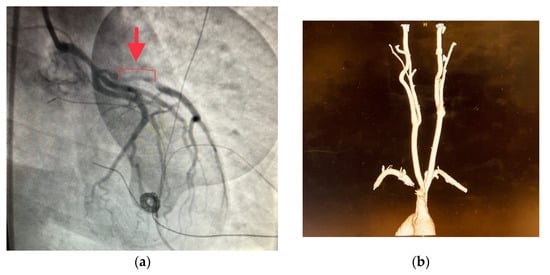

KC was admitted to the hospital on 31 August 2021 with severe chest pain after exercise and was noted to have anST elevation myocardial infarction (STEMI) based on her ECG. Based on the ECG findings and the presence of probable cardiogenic shock (blood pressure 70/30), she was emergently prepped for a coronary angiogram. SCAD was found in the distal left main and proximal left anterior descending artery (see Figure 1a). Based on her clinical picture, a decision was made to intervene. She received percutaneous coronary intervention with two overlapping drug eluting stents in the proximal left-sided circulation and an intra-aortic balloon pump was placed. She was started on dual anti-platelet therapy (DAPT) as well as unfractionated heparin. Her chest discomfort resolved immediately after the procedure. An echocardiogram that day conveyed an ejection fraction of 35–40% with severe hypokinesia of the anterior wall and akinesia of the apex. She was subsequently started on a beta blocker and ace inhibitor. The following day, she described 10/10 pain in her left lower extremity. Her leg was noted to be swollen with severe pain to palpation around the entire calf region. Her pulses in her foot were not palpable. She was emergently taken to the operating room for fasciotomy in the setting of compartment syndrome, likely related to the DAPT and heparin causing a spontaneous bleed. KC ultimately recovered and was seen for follow up in the office.

Figure 1.

(a) Cardiac catheterization showing the dissection of the proximal left anterior descending artery of patient KC. Cardiac catheterization conveying the dissection of the distal left main coronary artery and the proximal LAD (arrow). (b) CTA neck of patient KC. CTA of KC showing FMD involving the distal left internal carotid artery (arrow). There is a focal smooth short segment enlargement of the distal left cervical internal carotid artery. (c) CT chest of patient MC. CT of MC showing a mildly aneurysmal ascending aorta, measuring 4 cm.